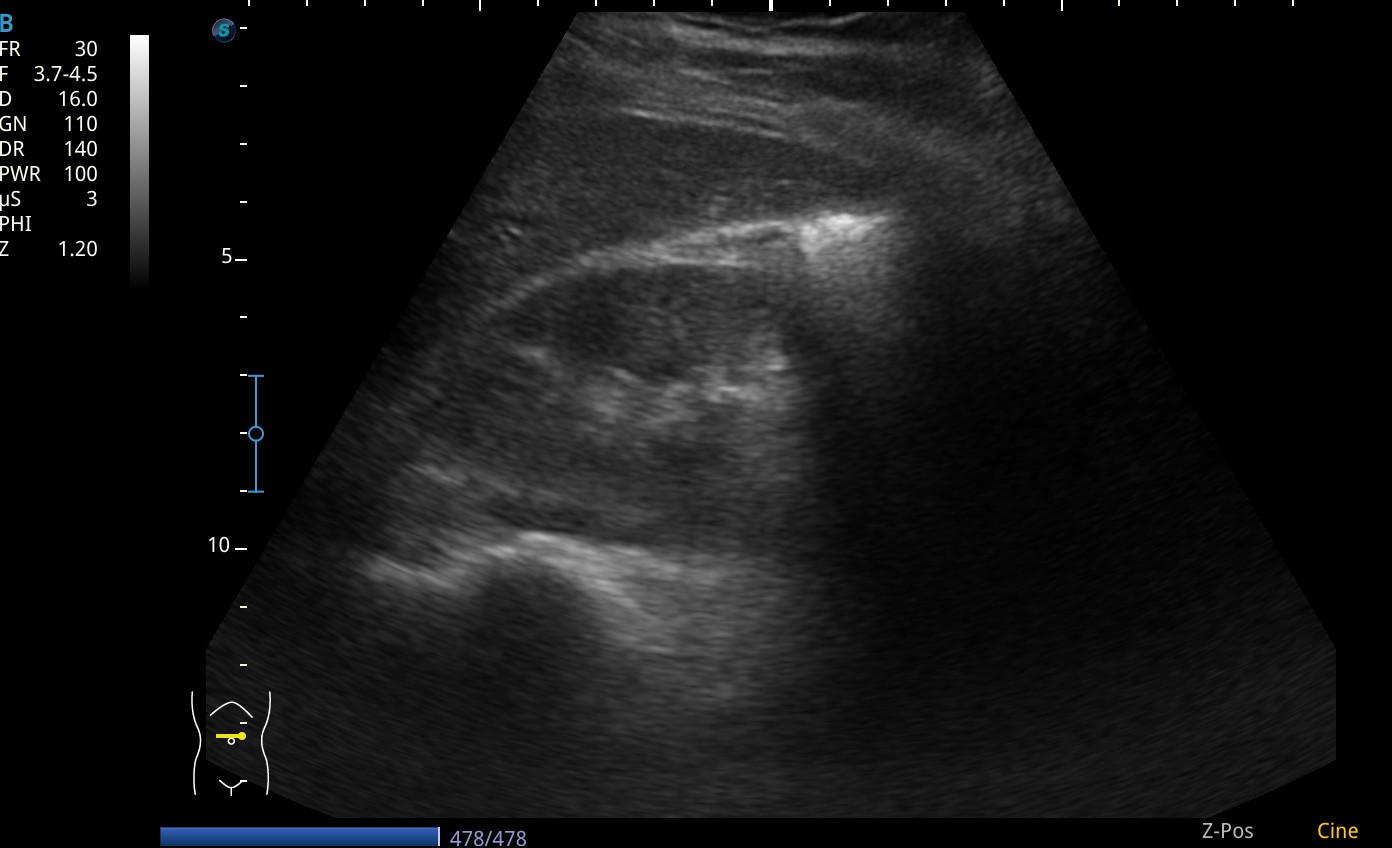

Se realiza ecografia a pie de cama que muestra como en el flanco derecho presenta silueta renal con un polo superior visible, sin poder definir el polo inferior, y la misma imagen en la silueta renal izquierda.

Asi mismo vemos a nivel de epigastrio bajo (zona umbilical), tejido sugestivo de parénquima renal que cruza por delante de grandes vasos, imagen compatible con un riñon en herradura.

En pelvis renal izquierda se aprecia una imagen hiperecogénica, sugestiva de microlitiasis.